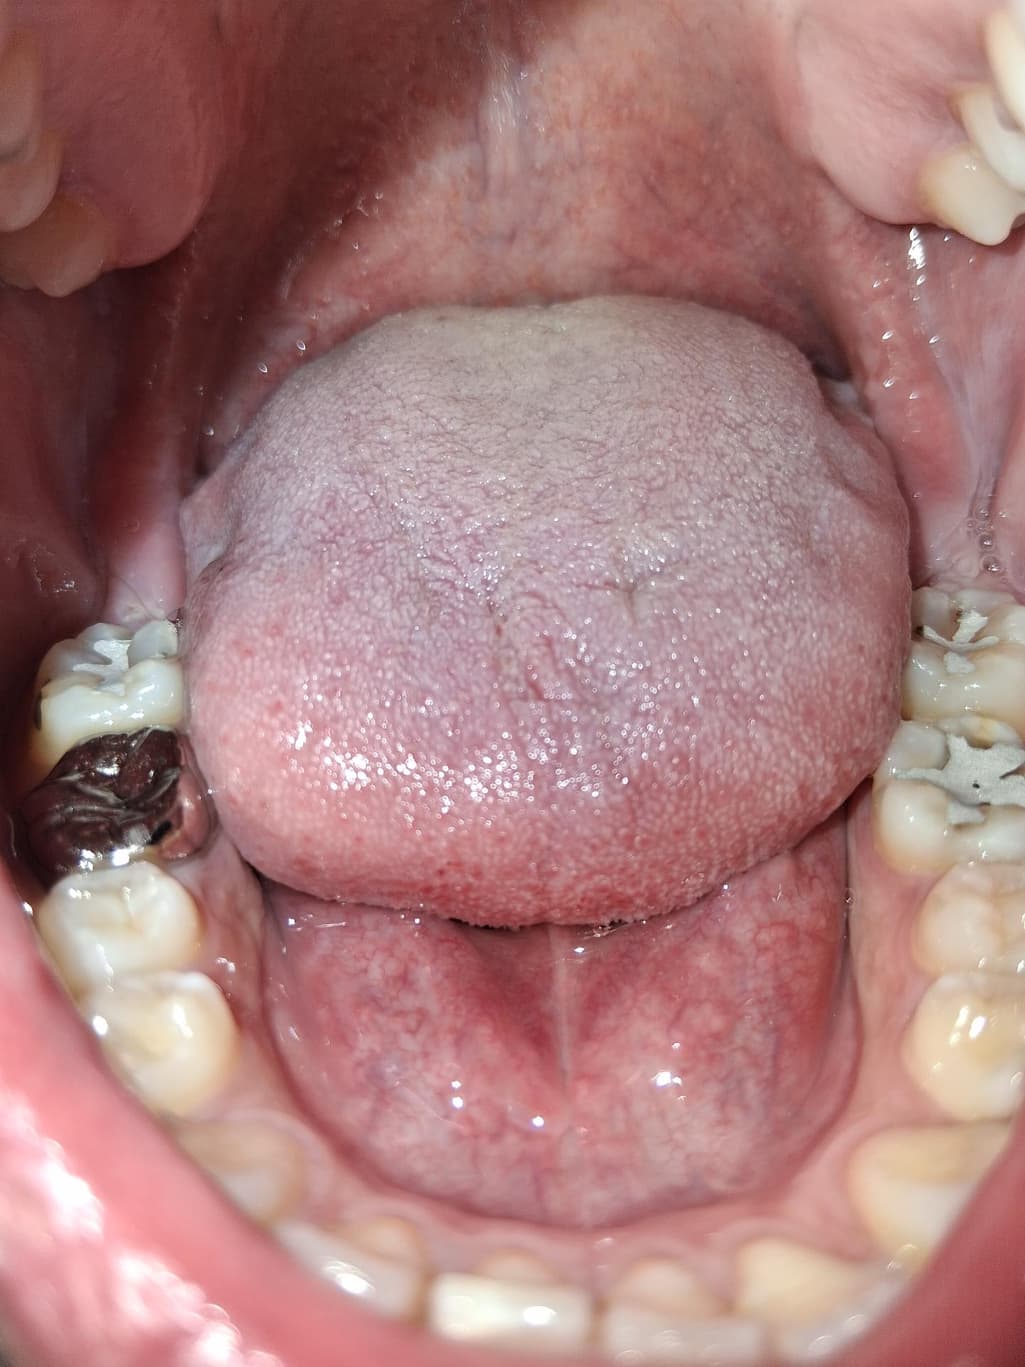

어제부터 씹을 때 아파서 보았더니 몇 년 전에 사랑니 뽑았던 자리에 하얀색 무언가가 자랐습니다.

가만히 있을 땐 안아프고 어금니 꽉 깨물거나 씹을 때 통증이 있습니다. 며칠있으면 통증이 사라질까요?

아마 잇몸이 치아에 씹히면서 생긴 상처 같습니다. 잇몸이 자라서 그런거 같으니 계속해서 불편하면 잇몸을 조금 절개 하는 시술을 하시면될것같습니다.

사랑니를 발췌한 무의 잇몸이 하얗게 보이는 원인은 여러 가지가 있을 수 있습니다. 그 중에서 하나가 위쪽에 있는 치아가 아래에 있는 잇몸을 눌렀을 경우에도 불편감이 있을 수 있습니다. 이런 경우 잇몸을 누르는 부분을 다듬어주거나 잇몸을 누르는 사랑니를 발치한다면 해당 증상이 줄어들 수 있습니다.

사진만 봤을 때에는 구강 내 상처가 생긴 것으로 보입니다. 며칠 지켜보시고 계속 불편시 치과 가보시면 됩니다.

잇몸과 볼쪽에 궤양성 병소가 보이긴 하는데 사진만 봐서는 정확한 진단은 어렵습니다. 구강내과 가보시기 바랍니다.